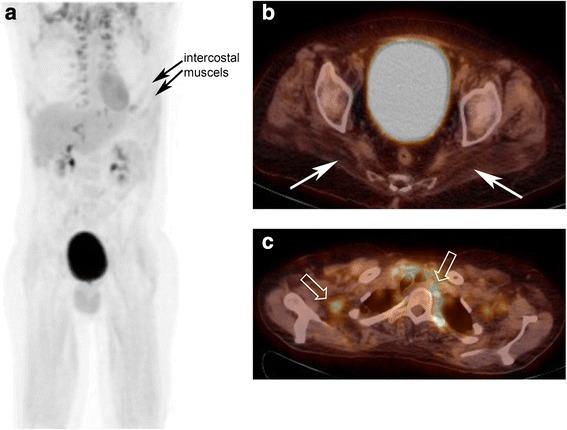

None of the muscles analysed showed a focally increased FDG-uptake. Thus, quantification of muscle glucose metabolism could not be calculated. However, increased FDG-uptake, i.e., increased glucose utilisation, was observed in the respiratory muscles of one patient with severe, restrictive respiratory failure. In contrast, specific MRI sequences showed oedematous as well as atrophic muscle areas in PD.

分析的肌肉中均未显示局灶性 FDG 摄取增加。因此,无法计算肌肉葡萄糖代谢的定量。然而,在 1 名患有严重限制性呼吸衰竭的患者的呼吸肌中观察到 FDG 摄取增加,即葡萄糖利用增加。相比之下,特定的 MRI 序列显示 PD 患者的肌肉有水肿和萎缩区域。